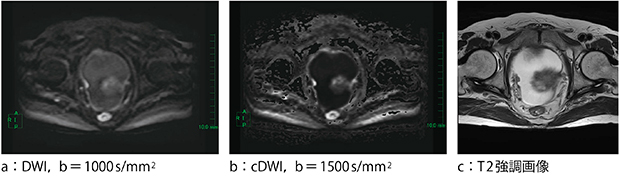

1.前立腺(図5)

前立腺は,b=1000s/mm2(図5 b)では不十分であり,b=2000s/mm2(図5 c,d)とすることで病変部がコントラスト良く明瞭に描出される。

また図5 dは,cDWIによるb=2000s/mm2の画像であるが,通常のb=2000s/mm2(図5 c)と比較しても遜色のない画像となっている。

図5 前立腺